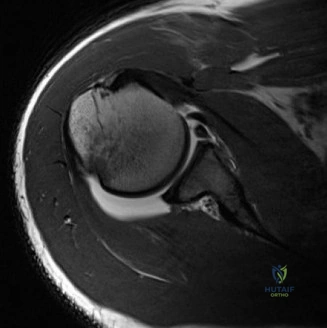

Anterior shoulder instability represents the most common major joint dislocation encountered in orthopedic practice, disproportionately affecting young, active, and athletic populations. While the classic Bankart lesion—an avulsion of the anteroinferior capsulolabral complex—was historically considered the essential lesion of anterior instability, contemporary orthopedic understanding has shifted dramatically toward the recognition of osseous defects. Glenoid bone loss, often occurring in tandem with humeral head defects (Hill-Sachs lesions) to create bipolar bone loss, fundamentally alters the biomechanical stability of the glenohumeral joint and dictates surgical decision making.

The epidemiology of anterior instability highlights a high recurrence rate, particularly in patients under the age of 20 engaged in contact sports. Recurrence rates following non operative management in this demographic can exceed 80 percent. Even following arthroscopic soft tissue stabilization, recurrence rates remain unacceptably high if critical glenoid bone loss is unrecognized or inadequately addressed. The incidence of significant glenoid bone loss in recurrent instability patients is estimated to be between 20 and 40 percent. The morphology of this bone loss typically manifests as attrition or fracture of the anteroinferior glenoid rim, transforming the normal pear shaped glenoid into an "inverted pear" configuration.

Advanced imaging is mandatory when bone loss is suspected. While Magnetic Resonance Imaging or MR Arthrogram is excellent for evaluating the capsulolabral complex, rotator cuff, and cartilage, three dimensional Computed Tomography is the gold standard for quantifying osseous defects.

The en face view of the glenoid on 3D CT with the humeral head digitally subtracted allows for precise measurement. The "best fit circle" method is commonly utilized. A circle is drawn matching the contour of the inferior and posterior glenoid, and the area or width of the missing anterior bone is calculated relative to the area or diameter of the circle. The Pico method compares the surface area of the injured glenoid to the contralateral normal glenoid, assuming the contralateral shoulder is uninjured. The humeral head must also be evaluated to calculate the glenoid track, measuring the width of the Hill-Sachs lesion and the intact anterior glenoid bone bridge.